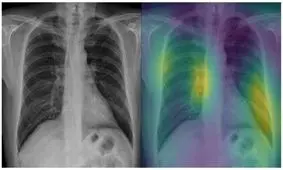

گروهی از دانشمندان در اسکاتلند راهی برای تشخیص حضور ویروس کرونا (کووید-۱۹) در بدن افراد با استفاده از اشعه ایکس پیدا…

پژوهشگران برزیلی، یک مدل مبتنی بر هوش مصنوعی و اشعه ایکس طراحی کردهاند که میتواند به شناسایی سریع کووید-۱۹ کمک کند.